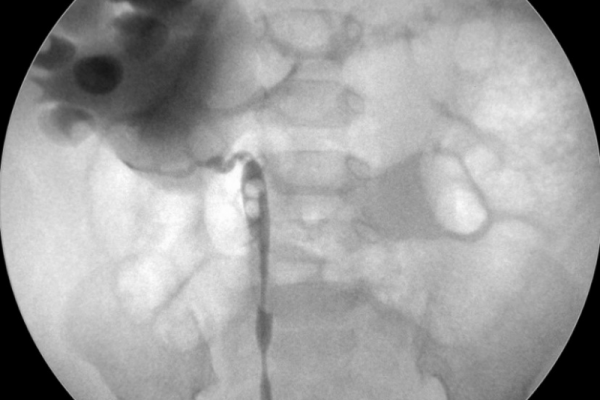

Hydronephrosis

Hydronephrosis is swelling of the kidney due to a build-up of urine, usually caused by a blockage. We identify the cause through imaging and manage it with procedures to relieve the obstruction and preserve kidney function.

5b520634-5678-4ad2-8cc6-5cea25bbab96

PUJ Obstruction

Pelvi-ureteric junction (PUJ) obstruction is a narrowing where the kidney meets the ureter, leading to poor drainage and swelling. It can be corrected with minimally invasive or robotic surgery to restore normal urine flow and protect kidney health. The robotic system is only available in the NHS at present.